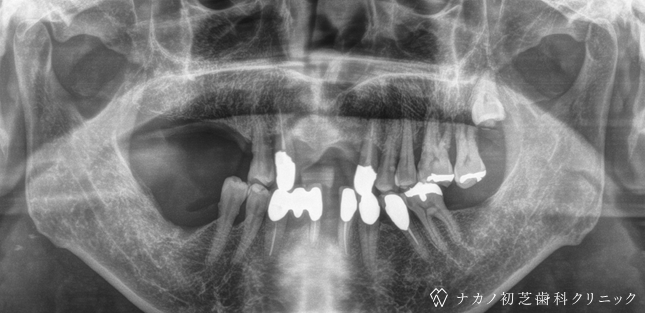

インプラント・13本 (60代女性)

BEFORE

AFTER

年齢 60代女性

治療内容 インプラント治療13本(骨造成の併用)

インプラント治療とは、歯を抜いた所にチタン製の人工歯根を埋入し、その上に歯を入れる方法です。骨を増やすことで、より審美的に治療が出来ました。費用 1本 400,000円(税込 440,000円)

リスク・副作用

腫れ・疼痛・違和感を感じるなどの症状を生じることがあります。